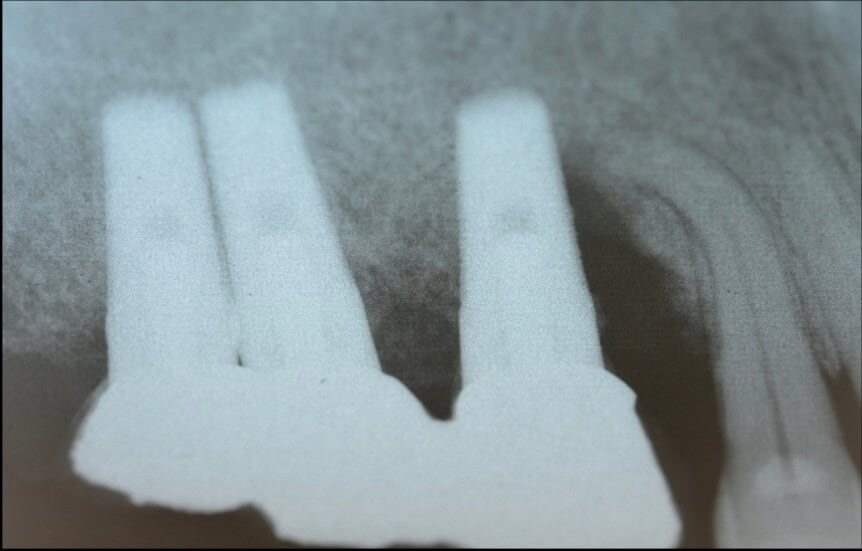

What we know about the bone response to compression comes from some classic histology studies from the Gothenburg team of Lindhe, Lang, Berglundh and Abrahamsson (3). The team placed implants in dogs and conducted histological measurements at certain time intervals thereafter, looking closely at the histological progress of osseointegration.

The “big deal” however was on the implant they used: It looked like Straumann, but it was not.

Not only it had very protruding threads, but there was an additional “pitch” at the top of each thread which would have probably made the traditional Straumann users of that time scream in disgust! So this implant never made it to humans, but remained in the notoriously small market of Beagle-dog implants. Nevertheless, this design was genius for the purpose of the experiment, as it created areas of compression (at the pitch of each thread) and areas of no contact, or empty chambers in the surface between two threads.

Right after implant placement, friction stability was achieved thanks to the pitches of the threads biting tight into the bone walls, while the non-contact areas filled with blood clot. The big news came however on the 4th day, when an interesting pattern of bone resorption occurred at the coronal side of the pitch! Why resorption? Obviously the compression of the bone there had killed a zone of bone about 50 μm, which was now being cleared away.

And why the top of the pitch and not the bottom? Well, this is actually screw mechanics. Regardless if you work with implants or with IKEA furniture, screws only apply force through the side of the thread which faces their side of insertion. A screw thread has actually only one working side. We learned this well when we were slicing implant-abutment junctions, only to see how little surface of the actual screw is engaging with the implant and always only the coronal part. (We learned a lot by looking at screws that time, but that would be probably a topic for another post). Common engineering never ceises to amaze!

Back to our histology study, the observation of the 4th day was actually an “aha” moment for all. It showed how compression kills bone and initiates resorption early after placement. This observation seen however in isolation made many clinicians to blame extensive threads as “bone killers”, starting the perception of implants with shallow or few threads as being “passive”. (It was also probably the reason why this experimental implant remained forever a dog-implant).

To get the whole picture, we need to look closer at the other side of the coin and see what happens in the no-contact areas. There, at 1 week one could see another exciting development: contact osteogenesis! New mineralized bone was created on the surface of the implant in the empty chamber, where previously only blood clot existed. This was something hardly seen on the smooth surface implants, but was apparent in the SLA implants introducing another factor in the equation, the implant surface.

The collective message of these amazing experiments was the while bone is being cleared at the pitch of the thread, new bone is getting created on the implant surface at the no-contact areas! Surface is a significant factor here, with contact osteogenesis being well established at 2 weeks in humans with SLAactive implants, as documented by another great study by Lang et al (4). Lang as well, noted absence of new bone at the pitch of the thread after 1 week, but significant new bone in non-contact areas, where the “jumping” distance between the implant and the bone was short. Again, this message seen somewhat superficially, lead many to believe that the lower and fewer the implant threads, the better the implant would be, reinforcing the anecdotal concept of “aggressive” and “passive” implants. But as you can’t judge a book by its cover, you shouldn’t also judge an implant by its threads! The missing part here was that an implant with few and shallow threads will be unlikely to offer adequate primary stability!